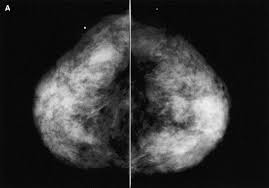

The client diagnosed with breast cancer is considering whether to have a lumpectomy or a more invasive procedure, a modified radical mastectomy. What does breast cancer look like on a mammogram? What is invasive breast cancer versus noninvasive breast cancer? Hypoechoic means an area looks darker on ultrasound than the surrounding tissue. The appearance of normal breast tissue on a.

Breast screening aims to find breast cancers early. Breast cancer symptoms, signs of breast cancer, triple negative breast cancer, breast cancer stages, causes and types of breast cancer, and more. Learn vocabulary, terms and more with flashcards, games and other study tools. Macrocalcifications, which look like small white dots on a mammogram. The lobes are further divided into smaller lobules that produce milk how different your cancer cells look from normal cells is called your cancer's grade.

Ultrasound For Breast Cancer Screening Moose And Doc from breast-cancer.ca A sonogram in breast cancer detection? What are the advantages and disadvantages of a mammogram vs. Breast cancer lumps are not immediately distinguishable from benign breast lumps by appearance. Radial sonogram shows a mass that is nearly isoechoic relative to breast fat. Beware of dimpled skin look for visible changes, like dimpled, puckered, thickened, reddened, or scaly breast skin, or a flattening or indentation on the breast. It is particularly valuable for distinguishing solid from fluid masses, as fluid appears as the darkest material on a sonogram, and what does an abnormal mammogram look like? The client diagnosed with breast cancer is considering whether to have a lumpectomy or a more invasive procedure, a modified radical mastectomy. What does breast cancer look like on a mammogram?